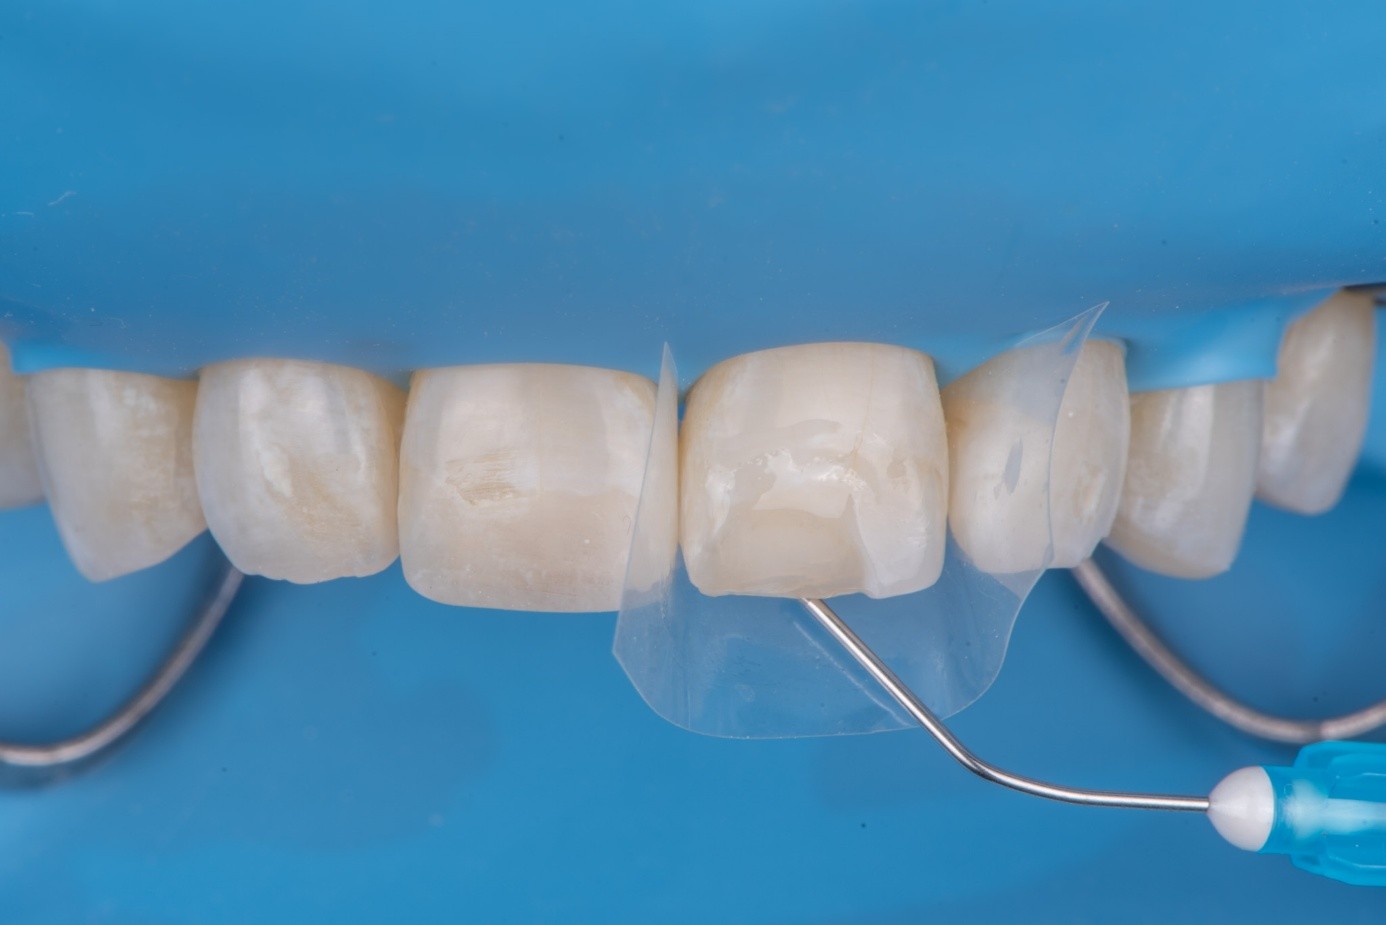

(14.) Intraoral view showing the fractured ceramic fragment positioned in place. The piece fits well, although minor gaps are present between the margins due to slight material loss, which can be restored using luting composite.

Figure 14

(15.) Intraoral view showing the fractured ceramic fragment positioned in place. The piece fits well, although minor gaps are present between the margins due to slight material loss, which can be restored using luting composite.

Figure 15

(16.) Intraoral view showing the fractured ceramic fragment positioned in place. The piece fits well, although minor gaps are present between the margins due to slight material loss, which can be restored using luting composite.

Figure 16

After achieving rubber dam isolation, the fractured composite segment was first air-abraded with aluminum oxide particles to clean and roughen the surface. It was then etched with phosphoric acid for 60 seconds, rinsed, dried, and treated with silane to enhance chemical adhesion (Figure 18 through Figure 20).8,9

The tooth surface was similarly air-abraded to remove biofilm and aged resin remnants, then selectively etched with phosphoric acid. Silane was applied intraorally to the exposed composite surface to promote bonding between the old and new composite layers.10 Following this, a universal bonding agent was applied to both the tooth surface and the fractured composite segment (Figure 21 through Figure 24).